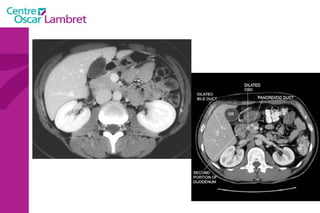

Les voies biliaires Une des fonctions du foie est la sécrétion de la bile. Elle est recueillie par  les voies biliaires  : Les voies biliaires intra hépatiques : Au niveau de chaque lobule hépatique, la bile sécrétée par les hépatocytes va être recueillie par un ensemble de petits canaux dont La réunion va former les canaux hépatiques droit et gauche qui s ’unissent au niveau du hile du foie en canal hépatique commun. La réunion du canal hépatique commun et du canal cystique forme le Cholédoque.

Les  voies biliaires extra hépatiques . La voie biliaire principale : Elle naît de la réunion des canaux hépatiques droit et gauche qui se réunissent pour former le canal commun qui va se réunir au canal cystique pour former le canal cholédoque, celui ci va s’aboucher au duodénum par l ’ampoule de Vater. La voie biliaire accessoire (la vésicule biliaire) : C’est un réservoir où s'accumule la bile dans l’intervalle des périodes de digestion. L’orifice de sortie est le canal cystique. Les voies biliaires

Il comporte 3 parties :  La tête: en arrière du bulbe, en dedans du deuxième duodénum et au dessus du troisième duodénum petit pancréas de Winslow ou crochet (processus unciforme) Le corps et l’isthme La queue: en contact avec le hile splénique (intra péritonéal) Le Pancréas

2 canaux : La voie biliaire principale. Le canal de wirsung (< à 5 mm) Débouchent dans le duodénum au niveau de l’ampoule de vater. La vascularisation est assurée par les branches des artères hépatiques, spléniques et mésentériques supérieures. Le Pancréas

Tube digestif Le Duodénum  : C’est la portion du tube digestif qui fait immédiatement suite à l’estomac, il commence au pylore et va jusqu’à l'angle de Treitz. Les 2ième et 3ième segments entourent la tète du pancréas (cadre duodénal). Il  a quatre portions  les canaux excréteurs du pancréas et des voies biliaires débouchent dans le deuxième duodénum.  Épaisseur pariétale 3 mm.